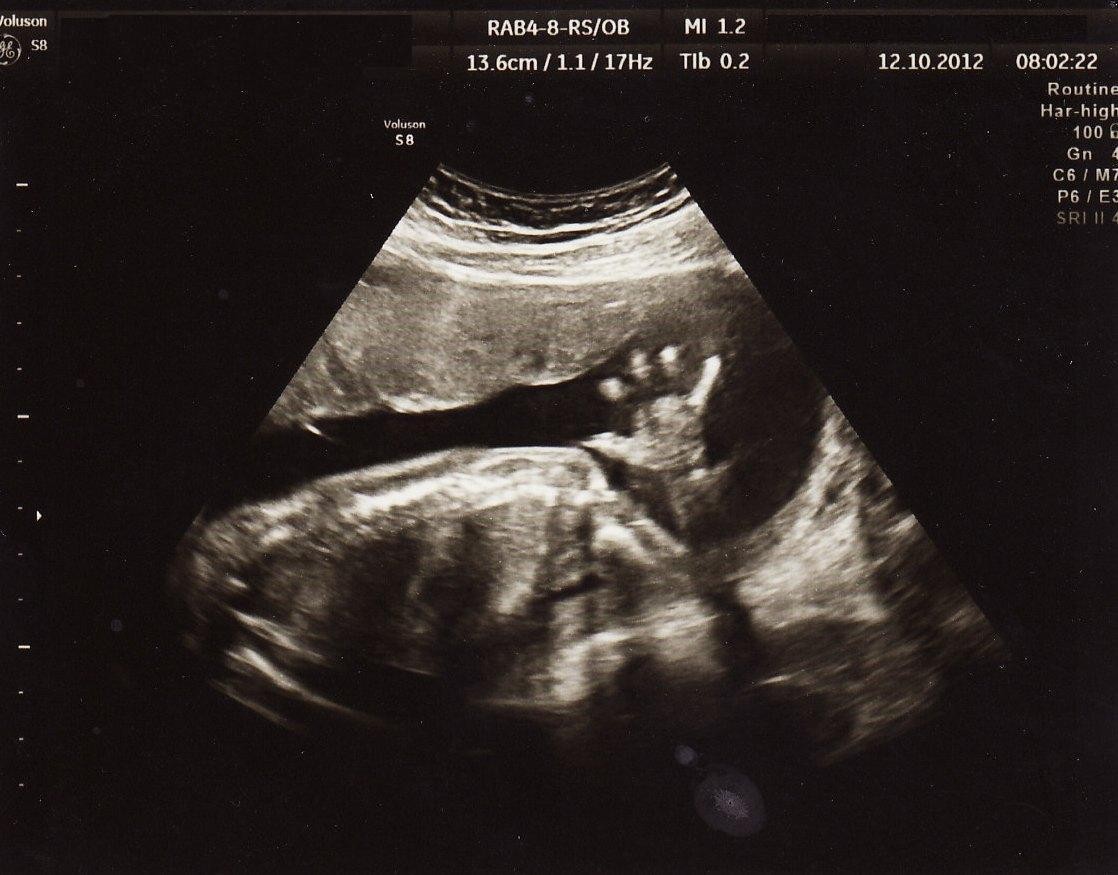

Pränatale Phase

..pränatale Aufnahme von Leonardo Cristiano und Matteo Alessandro Mitte Oktober 2012 (3 1/2 Monate vor dem voraussichtlichen Geburtstermin)